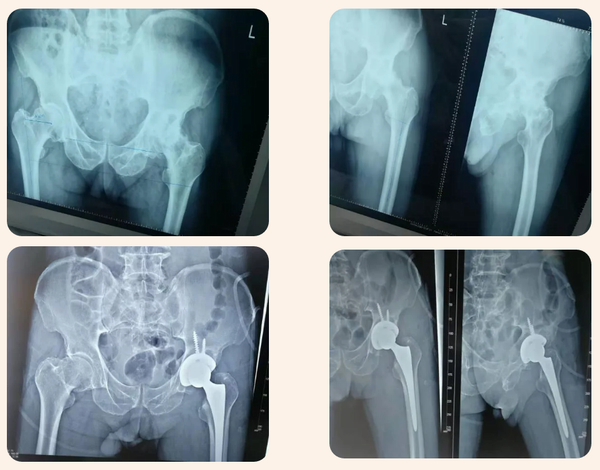

患者彭某某,男,77歲,因“左側髖關節疼痛5年余”來診入院。患者5年前在家無明顯誘因開始出現髖關節處疼痛,以左側疼痛較重,伴左膝關節疼痛,無發熱、無紅腫,無胸悶、呼吸困難、心悸、畏寒、發熱等癥狀,發病后曾到醫院就診,建議進行手術治療,患者不接受手術治療。近日患者左側髖、膝關節疼痛癥狀加重,到我院就診,門診以“左側股骨頭壞死”收住入院,入院后經積極完善相關檢查后診確為:1、左側股骨頭無菌性壞死;2、2型糖尿病。建議患者行左髖關節置換手術。

經積極做好術前準備后于11月1日在全麻下行左側全髖置換手術,手術順利,術后安全返回病房,術后第二天下地行走,術后給積極鎮痛、預防深靜脈血栓、術后康復等治療,術后順利康復出院。